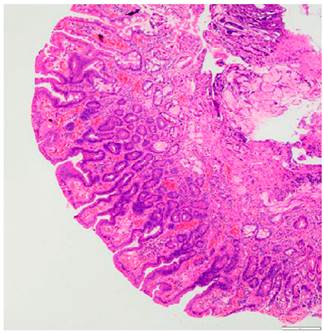

The patient underwent an ampulectomy of the minor duodenal papilla. Regarding the technique used during the procedure, the patient was under general anesthesia and was placed in a modified prone position. The second part of the duodenum was accessed using the duodenoscope and the major duodenal papilla was examined, where no abnormalities were found. An en-face view of the minor duodenal papilla was possible in the semilong axis, showing 10 millimeters of greater size adenomatous-like changes. The lesion was raised with normal saline solution + methylene blue (dilution ratio: 1:100 000) and an ampulectomy was performed using a diathermic loop. The specimen was retrieved with an endoscopic mesh basket and sent to the pathology service for analysis. There were no immediate complications. The following findings were described in the pathology report: a completely resected intestinal type tubular adenoma with low grade dysplasia (Figures 2 and 3).

A 73-year-old male with a history of endoscopic submucosal dissection of a lesion in the rectum (high-grade dysplasia tubulovillous adenoma) underwent an esophagogastroduodenoscopy due to dyspepsia symptoms and in which an approximately 10 millimeters adenomatous-like lesion was detected; appearance was found; when assessed with the duedonoscope the lesion was compatible with an approximately 10 millimeters adenoma of the minor duodenal papilla (Figure 4); there were no abnormalities in the major duodenal papilla. A tubular adenoma with low-grade dysplasia was reported in the biopsy report. No abnormal findings or evidence of pancreas divisum were reported on the magnetic resonance cholangiopancreatography. The patient underwent a papillectomy of the minor duodenal papilla; the technique used during the procedure similar to that described in case No. 1. There were no immediate complications. The following findings were described in the pathology report: a completely resected intestinal type tubular adenoma with low grade dysplasia (Figures 5 and 6).